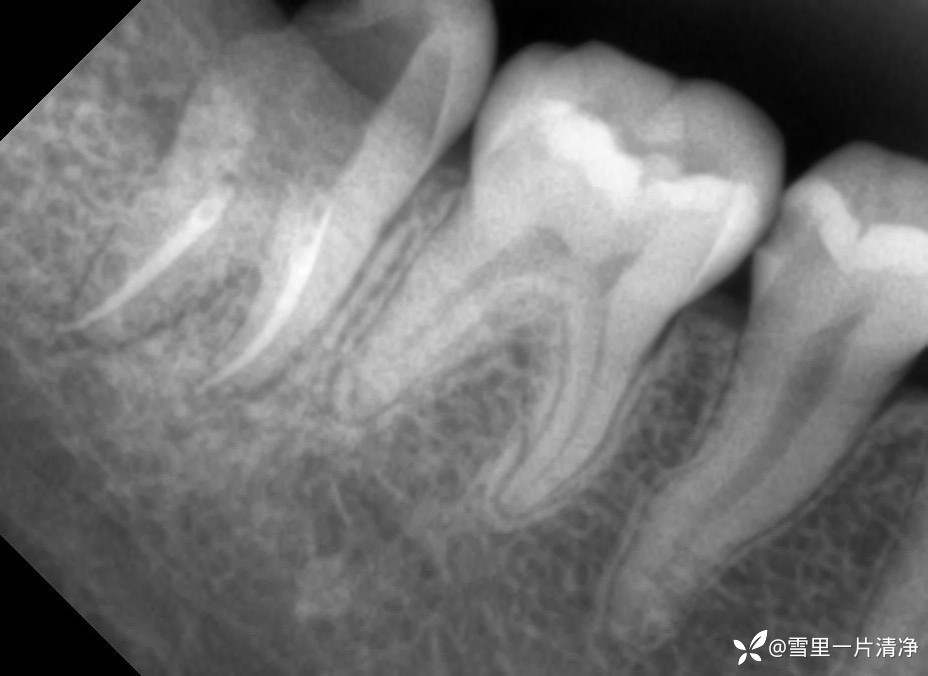

这里留个简单的片子你们可以发挥下想象你遇到了该怎么办